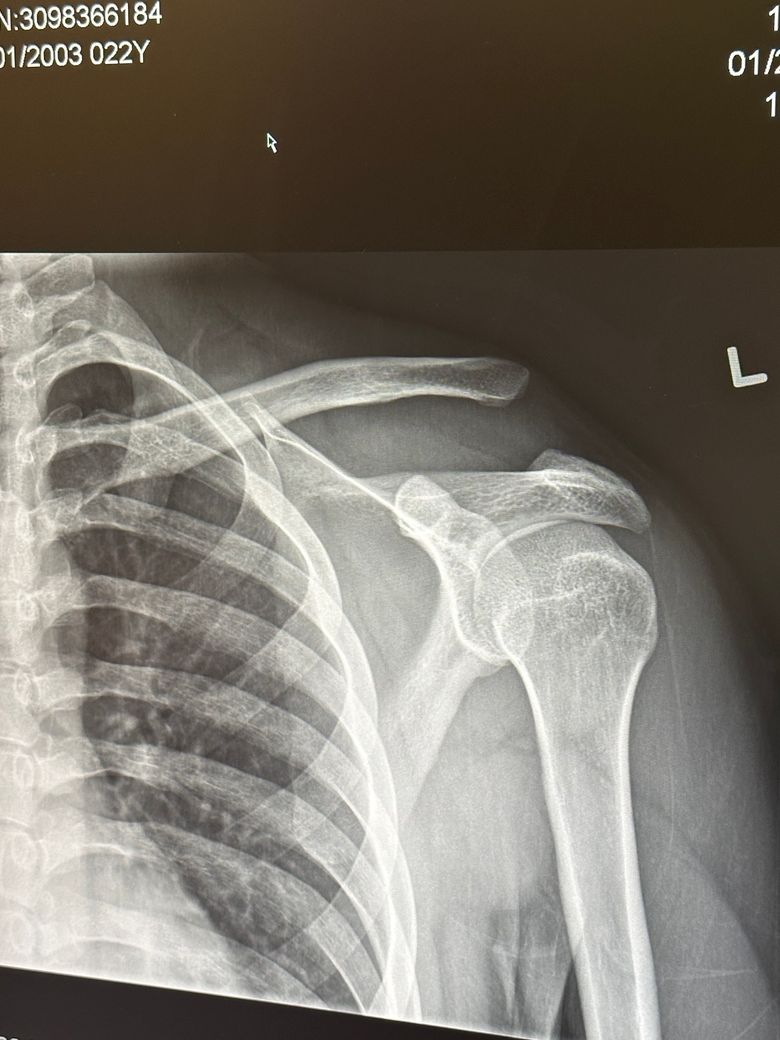

캐나다에서 스키를 타다가 심하게 넘어졌고 어깨를 바닥에 강하게 박았습니다 그리고 어깨가 움직이지 않아 급하게 캐나다 현지 응급실로 갔고 엑스레이도 촬영했습니다 여기 캐나다 병원에서는 문제가 없고 아직 젊으니 어깨 고정만 시키고 있으면 자가회복 된다고 하면서 설명하기를 나라마다 치료 방법이 다르니 걱정이 되면 한국으로 가서 다시 검사를 받아보라고 하더라고요..엑스레이 사진을 보여주었는데 비전문가인 제가 봐도 쇄골의 뼈가 그냥 이상하게 많이 벌어져 있습니다..제가 한국에 가더라도 다음주 수요일에 갈 수 있을 것 같은데요 그러면 다치고 10일이 지난 후 입니다

만약 심하게 다쳐서 견봉쇄골 탈구 5형으로 수술을 받아야 하는 상황이라면 10일이라는 시간이 지나고 수술을 받아도 문제가 없을까요..? 그리고 후유증도 걱정이 됩니다 타지에서 혼자 이러고 있자니 스트레스도 엄청나고 걱정도 많이 되서 잠이 안 오네요..제발 도움 부탁드립니다ㅠ

• 1번 째 사진